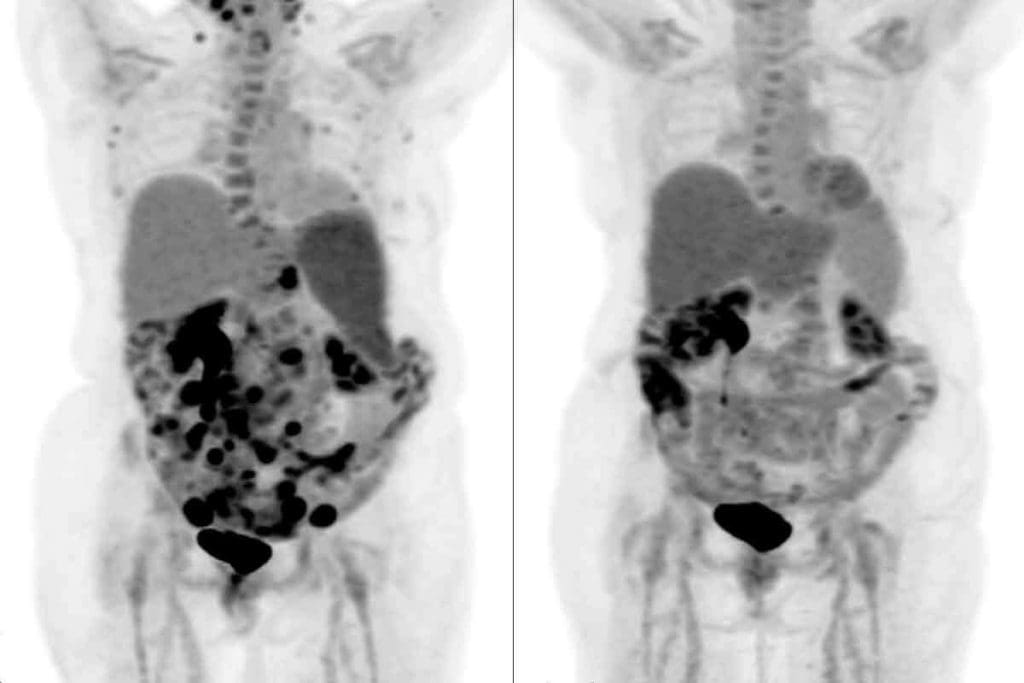

Visual Representation of Tumors on PET Images

The Warburg effect makes cancer cells take up a lot of 18F-FDG. This shows up as bright spots on PET scans. These spots mean there’s cancer.

Characteristics of tumors on PET images include:

1. High contrast between tumor and surrounding tissue

2. Clear delineation of tumor boundaries

3. Ability to detect metabolically active tumors

By understanding the Warburg effect and how it affects 18F-FDG uptake, we can see how PET imaging helps in finding cancer.

After diagnosis and staging, FDG PET scans help with treatment planning and response assessment. They show how tumors react to treatment, helping adjust plans if needed.

Being able to see treatment response early is very helpful. It lets us stop ineffective treatments and switch to better ones. This improves patient outcomes and quality of life.